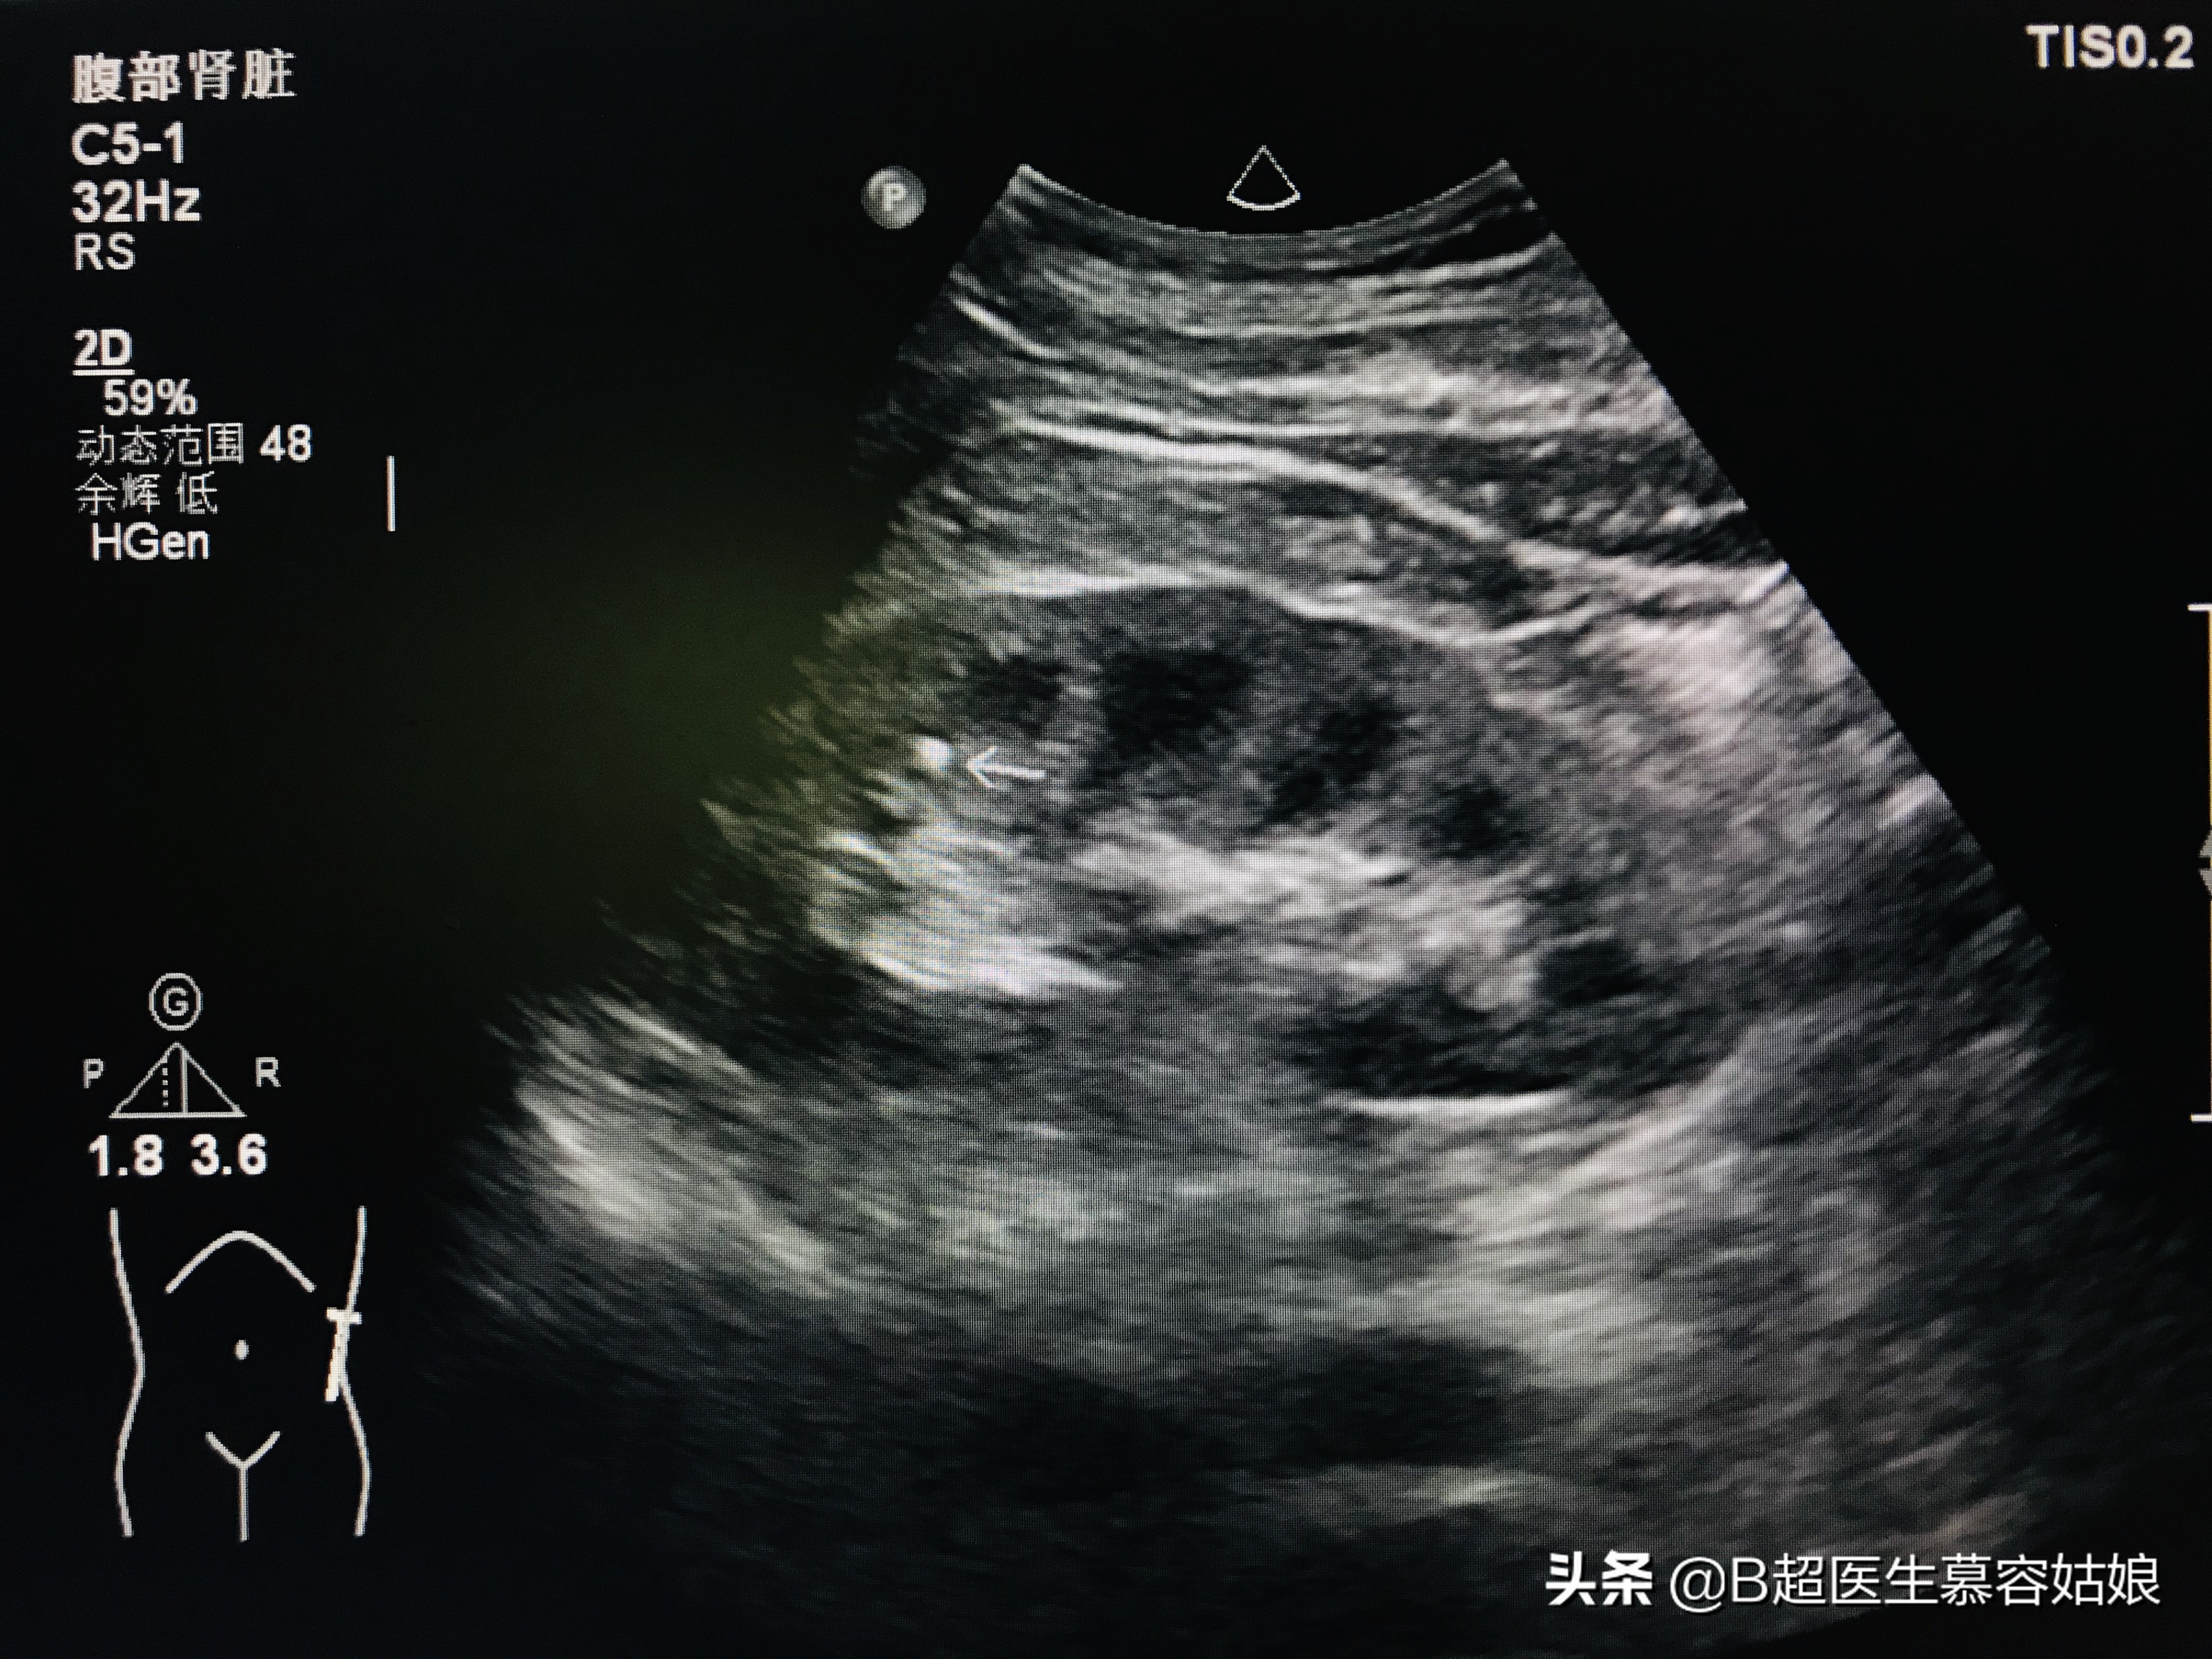

来看看超声图像上的肾结石是什么样子呢?

箭头所示亮点就是肾结石

肾结石多位于肾盂、肾盏内,上图小结石就位于肾盏内。什么是肾盏?